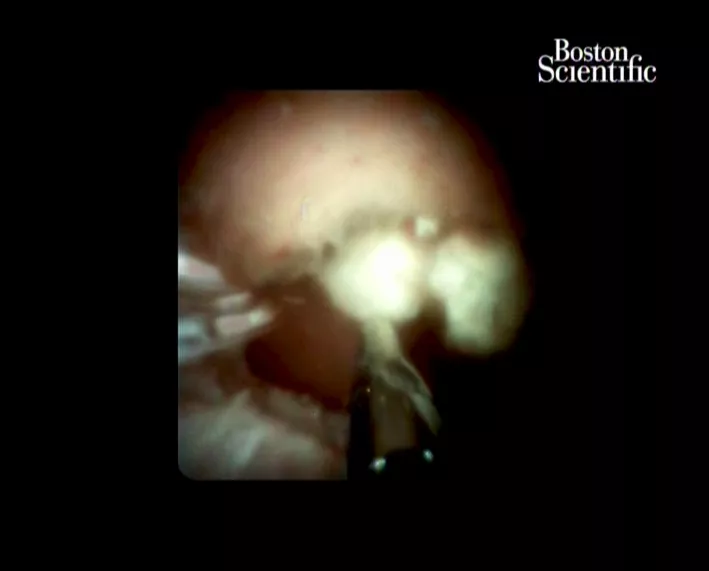

В Краснодаре врачи впервые в России провели операцию по удалению камней из протоков, сохранив при этом поджелудочную железу

В Краевую клиническую больницу № 2 поступил мужчина, который много лет страдал тяжелой хронической формой панкреатита, то есть заболеванием поджелудочной железы, когда в протоках образуются камни (вирсунголиты). Ранее пациентов с такими недугами лечили с помощью хирургического вмешательства, приводящего к инвалидности.

Особенность этого заболевания в том, что вирсунголиты очень твердые, к ним плотно прилегают стенки панкреатического протока. Поэтому у врачей не всегда получается ввести зонд, захватить и достать камни.

Сначала к мужчине применили наркоз. После этого в его двенадцатиперстную кишку ввели специальный аппарат, который разрушил камни электрическим разрядом. Из-за тока вирсунголит распался на несколько частей, которые врачи смогли захватить и вытащить зондом. Операция прошла успешно, сообщает пресс-служба минздрава Краснодарского края.